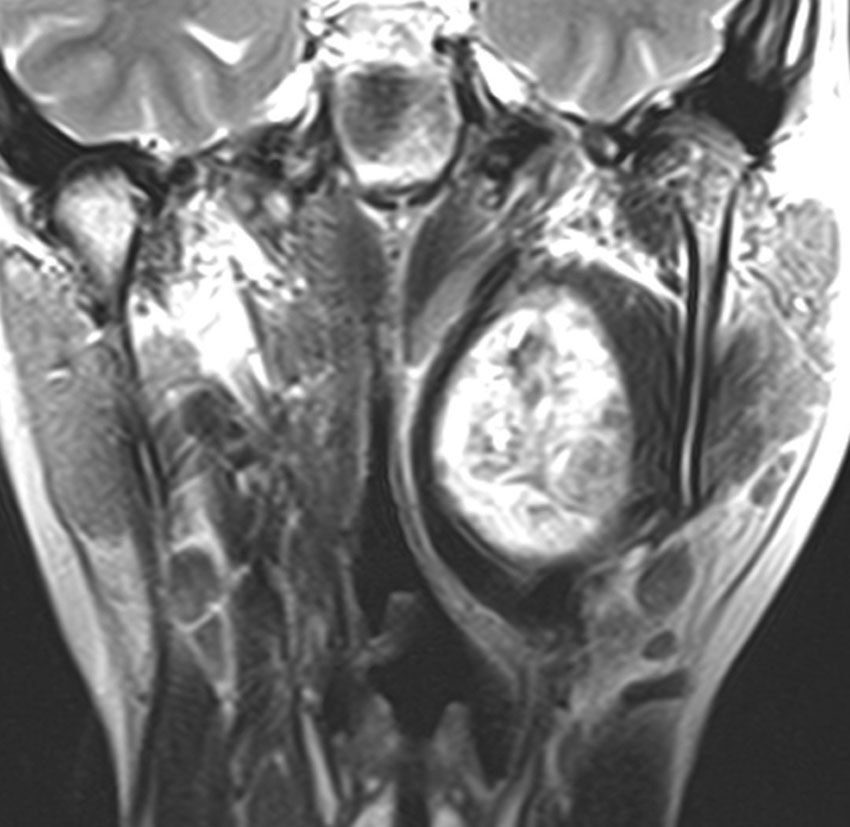

症例:頸静脈孔より下の深頸部のもの:副咽頭間隙腫瘍

左頸静脈孔の下の迷走神経節から発生したものです。ごく軽い飲み込み辛さだけが症状でした。

内頚動脈を強く圧排して,外形動脈からはかなり豊富な血流が流入しています。頭頸部外科で顎骨を割るような手術を計画されていました。

でも,右側の画像で見るような角度から,小さな頸部の皮膚切開だけで,胸鎖乳突筋だけを乳様突起から外して翻展して摘出できました。内部からほじくるように摘出すれば症状悪化はないのですが,周囲軟部組織から切断して剥離しようとすると厳しい嚥下障害と嗄声になります。

手術で全摘出しましたが嚥下障害などはでませんでした。普通のおとなしい神経鞘腫ですから再発はありません。